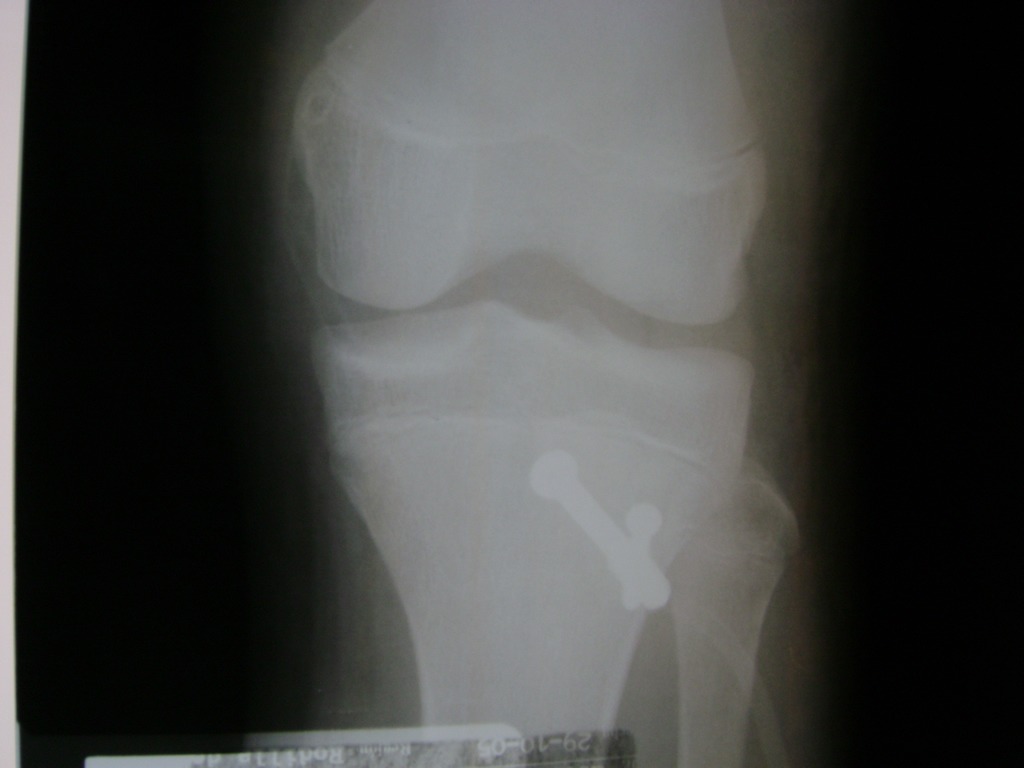

Cirugía de Fémur - Rodilla